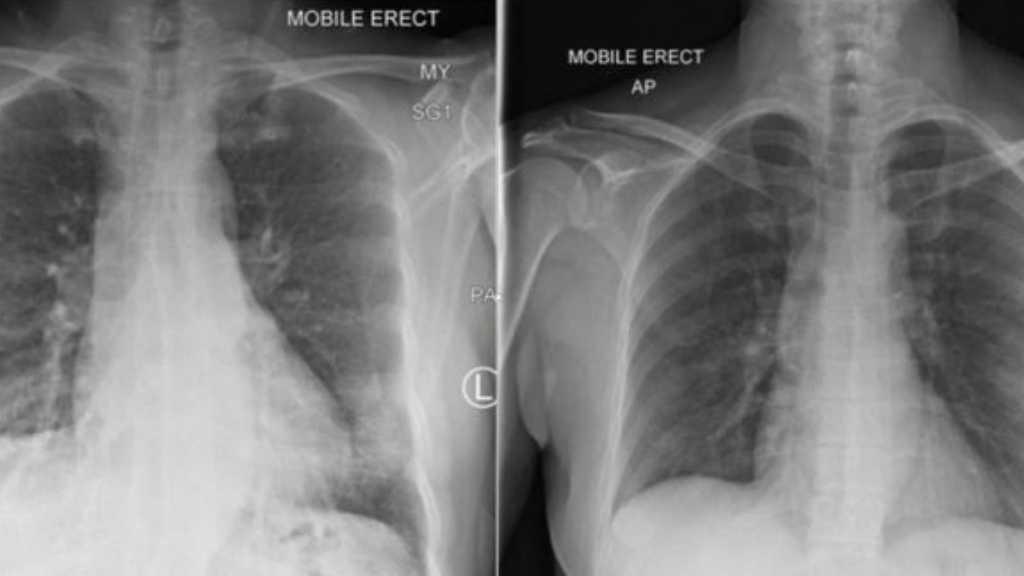

Prof Katherine Kedzierska bersama tim peneliti lainnya berhasil memetakan bagaimana cara kekebalan tubuh seorang pasien di Melbourne berhasil melawan virus korona. (Foto: ABC News/Loretta Florance)

Salah satu peneliti, Dr Carolien Van de Sandt, mengamati sampel darah pasien virus virus di laboratoirum. (Foto: ABC News/Loretta Florance)